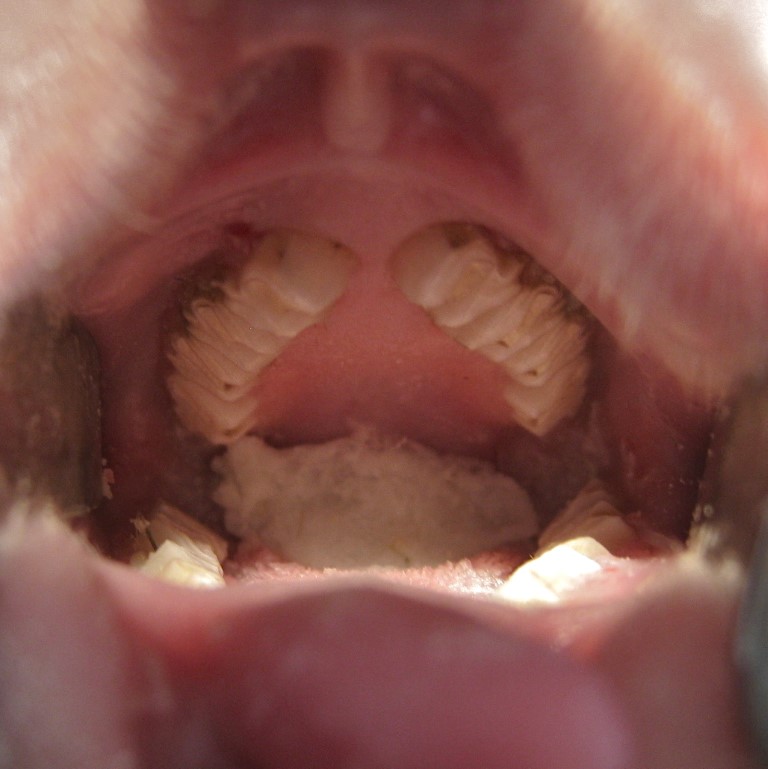

Veja abaixo alguns exemplos de tratamento dentário em Coelho, Chinchila e Porquinho da Índia:

COELHO: pontas dentárias em dentes inferiores, em direção à língua. Ao lado, o desgaste e nivelamento oclusal, com a remoção das pontas

PORQUINHO DA ÍNDIA: À esquerda, hipercrescimento de incisivos; ao centro, cavidade oral com dentes de tamanho e formato adequados e à direita, hipercrescimento de dentes posteriores inferiores em grau acentuado